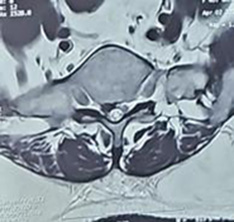

Following spinal anesthesia, patients were positioned prone. A midline incision was made one level above and below the involved segment. C-arm intensifier was utilized, especially when sacralization or lumbarization was identified in preoperative imaging. The spine and laminae were exposed, centering on the affected disc space. Portions of the spinous process and interspinous ligament were excised. The lower halves of both laminae were removed until the epidural fat became visible through the ligamentum flavum in the midline. (Fig. 1). The ligamentum flavum was excised bilaterally, and in certain cases, the overhanging portions of the hypertrophied medial facets were removed using a Kerrison punch. A standard technique was employed for discectomy, ensuring the complete removal of all visible disc material. Both nerve roots were examined for any additional compressive elements before they entered their respective foramina. For L5-S1 disc prolapse, only ligamentum flavectomy was performed with limited laminectomy (even less than the lower half) to facilitate adequate discectomy. The wounds were closed in layers after achieving proper hemostasis. For illustration images from a case of L5-S1 disc prolapsed are presented(pre-operative MRI and post operative X-ray) (Fig. 2-4).

Fig. 3. Axial T2-weighted MRI showing the central disc prolapse with right-sided protusion compressing the nerve roots